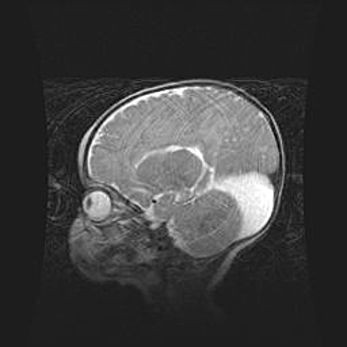

Мальформация Денди-Уокера. Киста задней черепной ямки.

Агенезия мозолистого тела.

Возраст: 2,5 месяца

Вес: 2420 г

Пол: женский

Окружность головы: 37 см

Срок гестации: 32 недели

Мальформация Денди—Уокера — редкий вид патологии ЦНС, представляющий собой врожденный порок развития каудального отдела ствола и червя мозжечка, ведущий к неполному раскрытию срединной (Мажанди) и латеральных (Лушка) апертур IV желудочка мозга. Для этогно синдрома характерна триада симптомов: гипотрофия червя мозжечка и/или полушарий мозжечка, кисты задней черепной ямки, гидроцефалия различной степени. В 70% случаев порок сочетается и с другими аномалиями головного мозга, в частности с агенезией мозолистого тела.